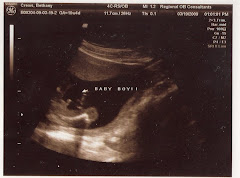

In this picture you can really see his back bone and his heart. The back bone is the curved white line at the bottom and his heart is the little black dot.

Here you can also see the heart and back bone really good.

Again he's showing off.